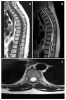

Paciente de 63 años con dolor crónico lumbar que consultó por reagudización del mismo con irradiación a ambos miembros inferiores durante la marcha; la exploración neurológica fue normal. Se realizó RMN de...

Caso completo | PDF

Neurología: Patología de raquisEtiología: OtrosDiagnóstico final: Quiste ependimario intramedularNivel de certeza: